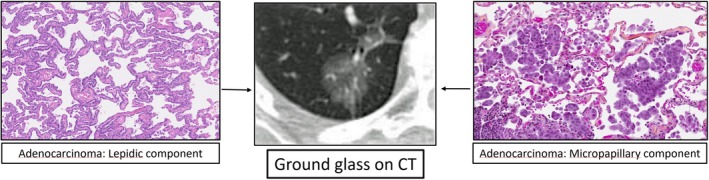

肺叶下切除术在早期肺腺癌的治疗中越来越受欢迎,通常在CT上表现为磨砂玻璃结节。然而,磨砂玻璃结节是一组异质性病变,它们经常被等同于原位或鳞状腺癌。许多病变在组织学上表现为高级别微乳头状分布,并表现为通过空气间隙扩散(STAS);与叶下切除术后复发率增加相关的特征。JCOG0802和CALGB140503试验中STAS影响的事后分析目前正在进行中,尚未发表。这篇简短的报告旨在提高人们对这些相关问题的认识,这些问题在接近早期肺腺癌的管理时应该考虑。

Sublobar resection is gaining popularity for the treatment of early stage lung adenocarcinoma, often presenting as a ground glass nodule on CT. Ground glass nodules are, however, a heterogeneous group of lesions, and they are too often equated with in situ or lepidic pattern adenocarcinoma. Many of these lesions actually harbor high grade micropapillary pattern and display spread through air spaces (STAS) on histology; features that are associated with increased recurrence following sublobar resection. Post hoc analysis of the impact of STAS in the JCOG0802 and CALGB140503 trials is currently ongoing and has yet to be published. This brief report aims to raise awareness of these pertinent issues that should be considered when approaching the management of early stage lung adenocarcinoma.